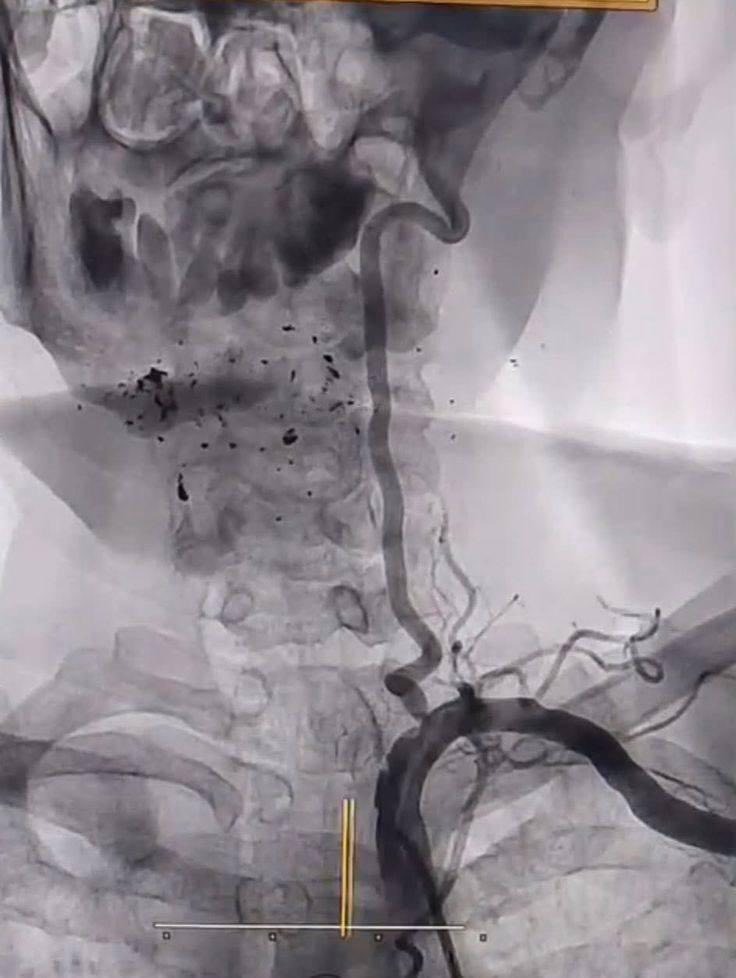

وأشار عبد الهادي إلى، أن المستشفى شهد إجراء عمليتين نوعيتين؛ حيث تمثلت العملية الأولى بـ فتح الشريان الفخذي الأيمن وزرع شبكة على يد الدكتور عزّت المياحي، بينما تضمنت العملية الثانية قسطرة لشرايين الدماغ أجراها بنجاح الدكتور إسماعيل السوز.